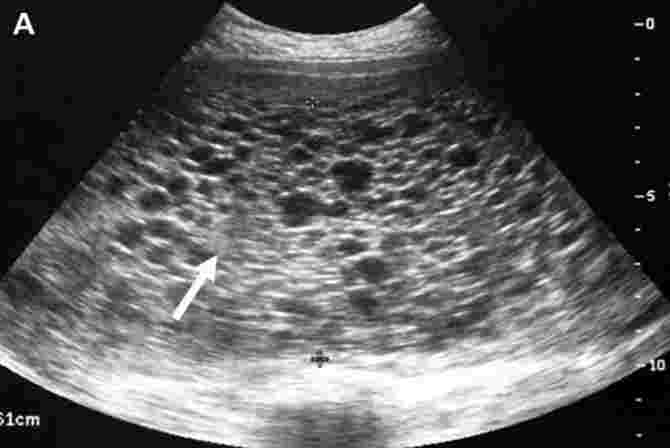

A molar pregnancy is when a foetus does not form properly in the womb and a baby doesn’t develop. A lump of abnormal cells grows in the womb instead of a healthy foetus. When a tumour develops in the uterus, the placenta swells into a mass of cyst-like sacs filled with fluid. Molar pregnancies make up for 1 in 1,000 pregnancies (0.1%).

This tissue looks like a large collection of grape-like cell clusters, and its growth is rapid compared to normal foetal growth.

The placenta grows and produces the pregnancy hormone, hCG. An ultrasound will show that there is no foetus, only a placenta.